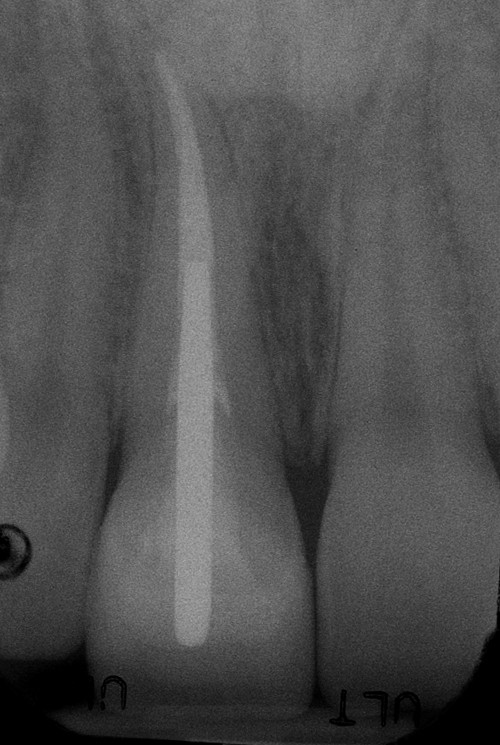

Before:Â Tooth #8 (upper right central incisor) has a history of trauma and root canal therapy. Re-treatment of the root canal filling was required.

After: Followed by delivery of a custom ceramic post/core foundation, and a bonded all-ceramic full coverage single restoration (crown).